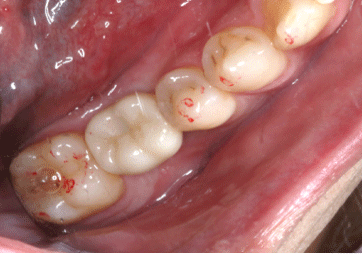

セラミック根幹治療

2024.12.1530代男性 根が割れた歯に意図的再植術を施したあとセラミックの被せ物で修復した症例